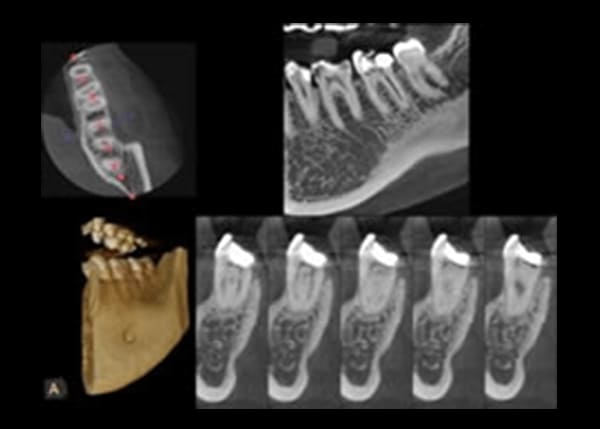

歯の根の治療は、状態により長期にわたってしまうことがあります。

通常のレントゲンからしか情報を得ていないと、ときに歯科医師自身も迷路に迷ったような状態になることがあります。

そこで、CTレントゲンの画像を見ることにより、根の状態がよく分かるようになります。そのため、無駄に長期間治療、根の治療を行うことがなくなります。